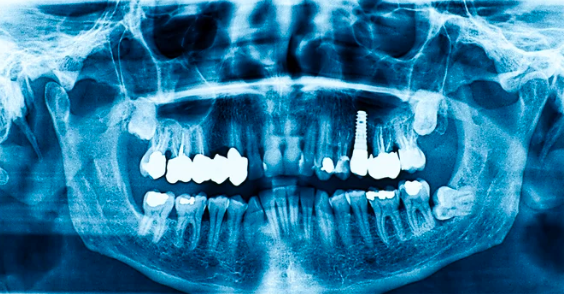

症例②

年齢50代男性

治療期間4ヶ月

治療内容セラミック治療、インプラント治療

治療箇所

インプラント:左下6番

セラミック:左上4番、5番、7番 左下7番 右下6番 右上5番

治療費用950,000円

セラミック治療

インプラント治療